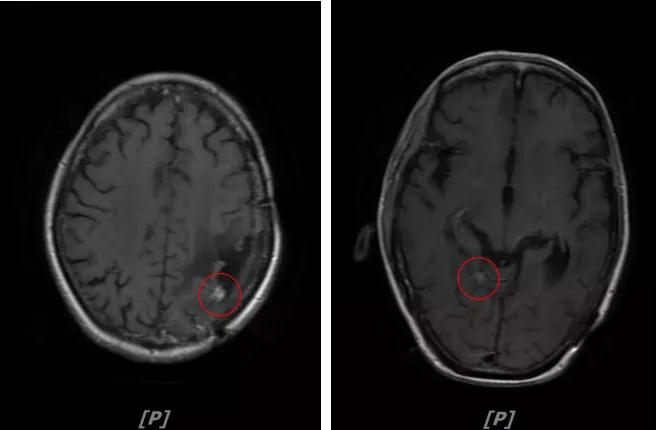

b.2014年3月全脑放疗结束后,予以LX方案治疗(拉帕替尼 1250mg qd+卡培他滨 1500mg bid)。每3个月规律复查,未见明显异常。下图为2014年6月患者行头颅增强MR检查,提示左顶叶脑转移瘤术后改变。

每3个月规律复查,未见明显异常。如2015年8月 头颅MR检查,提示:左顶叶脑转移瘤术后放疗后改变,对比前片2015年3月10日相仿。